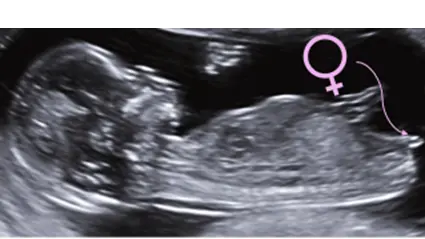

Revelación del Sexo Fetal

• ❤ Sabemos que conocer el sexo de tu bebé siempre será algo muy importante para ti, ¿Sabías que ya desde el primer trimestre podremos saber el sexo de tu bebé con una precisión de casi el 90%? A partir de la semana 16 ya se confirma el sexo en un 100%.

• ❤ La evaluación del sexo nos permitirá conocer algunas alteraciones de los genitales.

• ❤ Es importante también para descartar alteraciones genitales o enfermedades ligadas al sexo.